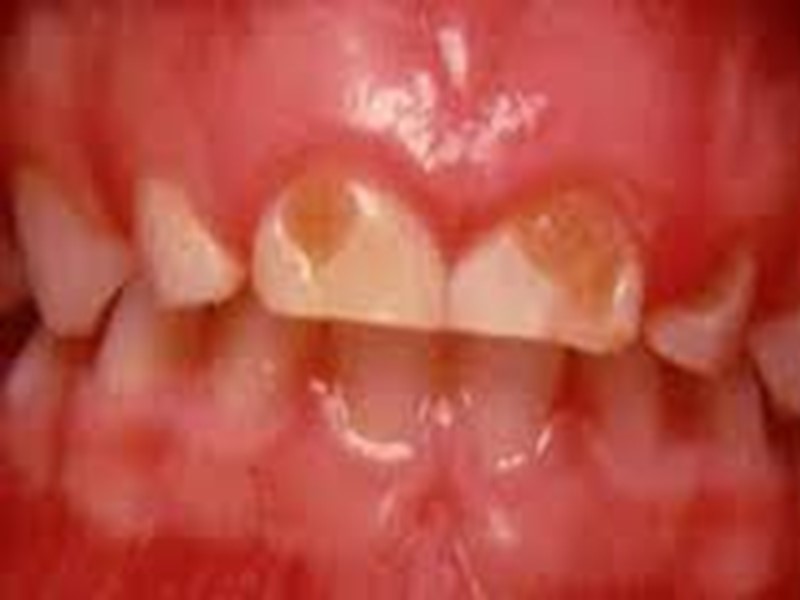

Классификация кариеса Начальный кариес (кариес в стадии пятна); Поверхностный кариес; Средний кариес; Глубокий кариес.

Классификация по локализации: Фиссурный кариес. Контактный (апроксимальный) кариес. Пришеечный (цервикальный) кариес. Циркулярный (кольцевой) кариес.

Клинические проявления кариеса зубов Кариес в стадии пятна (macula cariosa). Жалобы на боль, как правило, отсутствуют. В области пятна в отдельных случаях может появиться ощущение повышенной чувствительности к химическим раздражителям (кислое, соленое, сладкое). Если белое или пигментированное пятно расположено на вестибулярной поверхности фронтальной группы, то пациент может предъявлять жалобы эстетического порядка.

Диагностика начального кариеса Объективно: на поверхности эмали видно чаще одиночное меловое или пигментированное пятно диаметром 3-5 мм. Наиболее часто кариозные поражения локализуются в естественных углублениях зуба (фиссурах), контактных поверхностях, в пришеечной области.